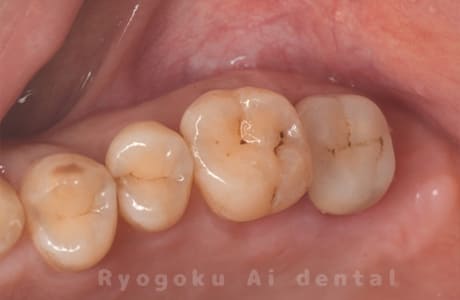

- 原因

- 左上6番重度カリエス

- 治療内容

- クラウンレングスニング

- 治療費用

- 44,000円(根管治療、補綴は別途費用)

他院で抜歯と判断された歯です。クラウンレングスニングを行い、保存を試みました。現在も問題なく被せ物が入り、使用できてます。

<リスク・副作用>

手術後は痛み、腫れ、痺れ、青あざなどの副作用が生じます。痛みは痛み止めを処方しますが、腫れ、青あざは1週間程度生じる場合があります。また、部位によっては神経の走行が複雑で、痺れが残り、長期的にお薬を処方する場合があります。